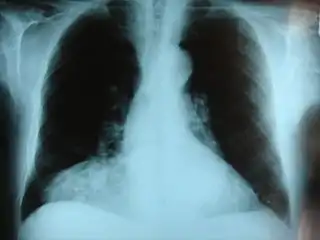

![]() Radiografía frontal del pecho mostrando una hernia de Morgagni. | ||